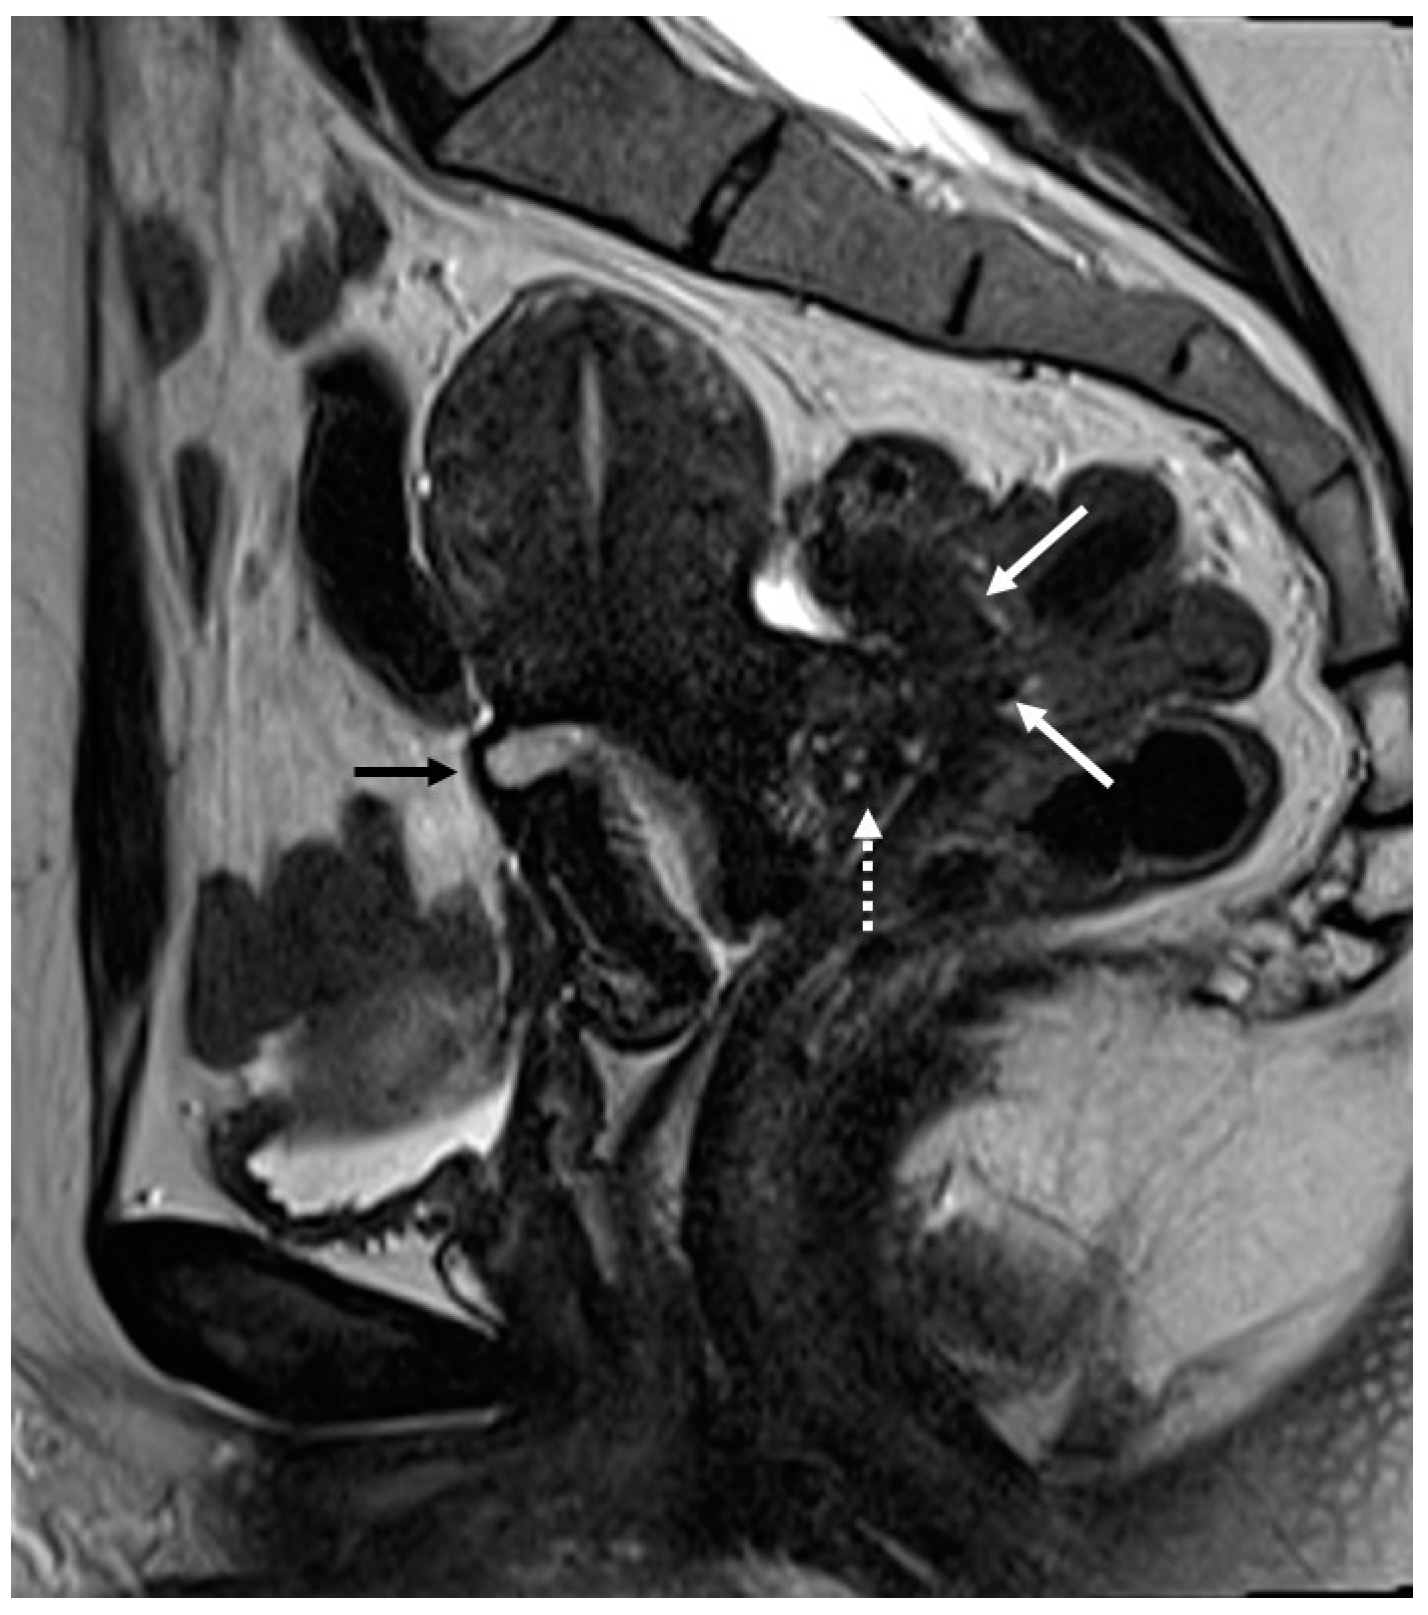

Figure 4.

Retrocervical endometriosis plaque, intestinal localization, kissing ovaries with bilateral ovarian endometriomas. (A,B) Axial T2WI; (C) Coronal T2WI. Hypointense retrocervical plaque (white arrowhead in (A)) localized in the uterine torus with involvement of the utero-sacral ligaments. Adhesions involve both ovaries with bilateral endometriomas (white arrows), which are prolapsed in a retro-uterine position and adhered to the utero-sacral ligaments and the recto-sigmoid junction. There is also an eccentric anterior parietal thickening in the recto-sigmoid junction suggestive of intestinal endometriosis lesion (white dotted arrow in (A)).

On an MRI, lesions appear as irregular thickness or nodules within the intestinal serosa or muscularis propria, hypointense at T2WI. They rarely affect the submucosa or the mucosa, and if infiltrated, we can observe edema and swelling in the area [7] (Figure 5 and Figure 6).

Figure 5.

External adenomyosis and intestinal endometriosis localization in 49-year-old female with story of multiple laparoscopy surgery. Sagittal T2WI shows a hypointense ill-defined subserosal mass in the posterior myometrium with hyperintense foci (long white arrow), suggestive for external adenomyosis, that cause retracting phenomena towards the anterior wall of the rectum. Additionally, there is deep endometriosis of the posterior compartment with hypointense nodule involving the serous and muscular layers of the anterior wall of the rectum (short white arrow).

Figure 6.

Retrocervical localization, intestinal mushroom cap sign and isthmocele in a 40-years old female. Retrocervical endometriosis localization (white dotted arrow), intestinal “mushroom cap sign” (white arrows) and isthmocele (black arrow).